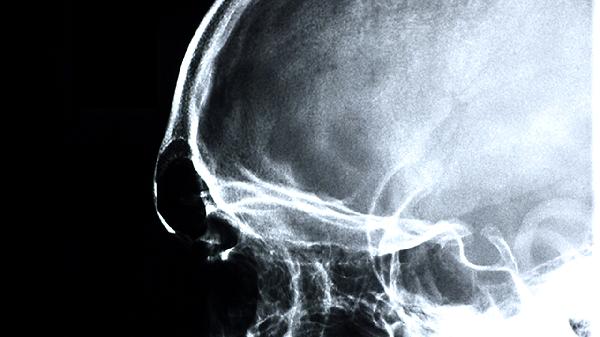

后脑被撞击后哪些反应要注意

后脑被撞击后需警惕头痛加剧、持续呕吐、意识模糊、肢体无力、视物异常等反应。这些症状可能与脑震荡、颅内出血、脑挫裂伤等疾病有关,建议立即就医排查。